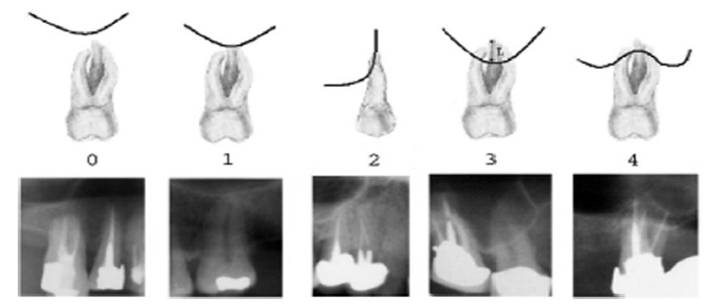

Materials and Methods: A total of 510 maxillary teeth from 85 patients were classified according to their topographic relationship to the maxillary sinus and measured according to their projection lengths on the sinus cavity using OPG and DVT modalities.

Results: In cases of classification 0, 85% and in classification 1 , 55.3% cases shows similar classification in both OPG and DVT. 28.5% of cases in both imaging modalities show classification 2. Only 15.9% of teeth roots exhibits classification 3. 11.1% of cases showed classification 4.The panoramic radiograph showed a statistically significant 2.24 times longer root projection on the sinus cavity in OPG comparison to DVT images.